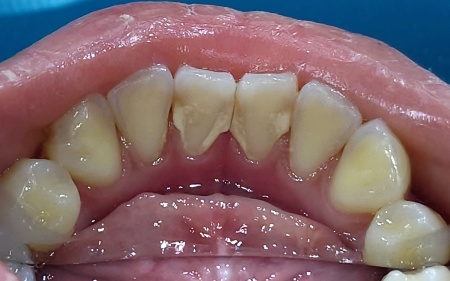

治療前

拝見したところ、下前歯の裏側に歯石が多く付着していました。

歯石とは、歯磨きで落としきれなかったプラークが、唾液中のカルシウムやリンと結合して硬くなったものです。

歯石は歯の表面に強くこびりついているため、通常の歯磨きで除去することは困難です。

また、歯石の表面はザラザラしており、虫歯や歯肉炎、口臭の原因となる細菌が付着しやすい特徴があります。

このまま放置すると、細菌が繁殖して口腔トラブルの原因になるリスクがあるため、しっかりと歯石を除去する必要があると診断しました。